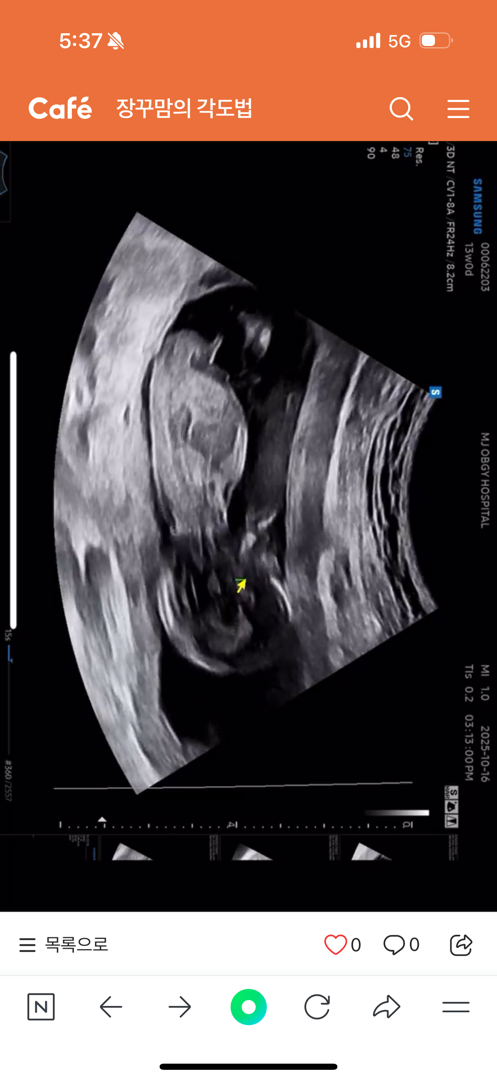

각도법한번봐주시면안될까용..!!!!

궁금해미쳐버림미다! 딸일까요 아들일까요!